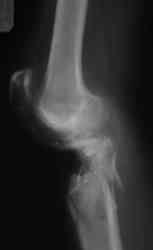

Уважаемые коллеги! На консультацию обратилась женщина, 23 года. В феврале огнестрельное ранение колена. Снимки первичные и майские в приложении. А также внешний вид раны. Укорочения конечности нет. Разгибание в коленном суставе отсутствует. Сгибание сохранено. Нестабильности нет.Дно раны - мертвая кость.

по снимкам у пациентки на данный момент сохраняется дефект наружного мыщелка б\б кости, который со временем приведет к вальгусной дефеормации голени и в настоящий момент практически отсутствует бугристость б\б кости, т.е. зона прикрепления собвственной связки, которую можно в принципе выкроить из средней порции сухожилия 4-хглавой со средней частью надколенника, но сначала необходимо запонить дефект костной ткани, либо путем свободной кости пластики, либо формированием отщепа б\б кости с микродистракцией в КДА Илизарова. т